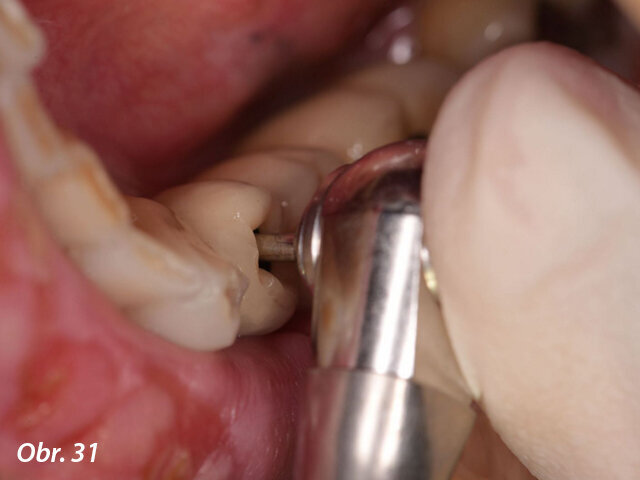

Po aplikaci lokální anestezie (Artikain 4 % s adrenalinem 1 : 100000) byly za použití řezu přes střed hřebene a intrasulkulárních řezů uvolněny mukoperiosteální laloky. Lingvální lalok byl přichycen stehem, aby byla oblast zákroku lépe viditelná (obr. 6, 7).